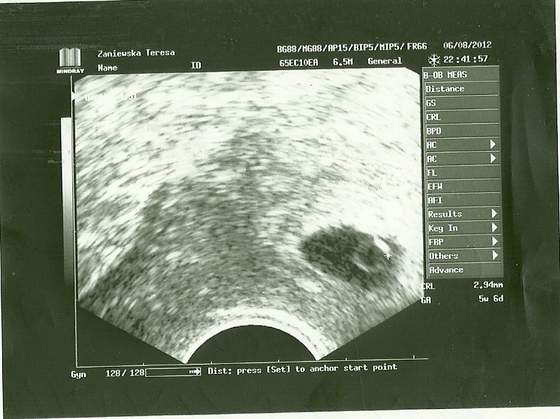

06,08,2012.jpg

To chyba dla mnie najfajniejszy na razie temat forum. Wasze zdjęcia aż mi buźkę rozweselają jak widzę te kruszynki. Też jestem marcówka. USG genetyczne mam dopiero wyznaczyć (od 1 do 19 września powinnam zrobić). Ale 6-go sierpnia będac na wizycie, która miała potwierdzić gdzie ciąża sie zagnieździła (bo było zagrożenie ponownej pozamacicznej) okazało się , że wszystko jest ok, serduszko biło jak oszalałe. Poniżej fotka. Zielone krzyżyki pokazują długość. Wtedy byłam w 7 tygodniu i 4 dniu ciąży.